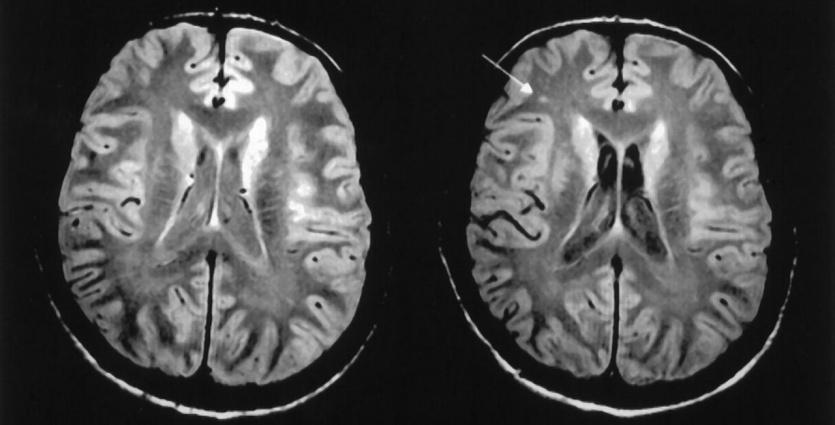

المادة البيضاء في الدماغ

المادة بالبيضاء هي عبارة عن نسيج يغطي الأجزاء العميقة من الدماغ، يتكون من ألياف عصبية تسمى المحاور العصبية التي تربط ما بين الخلايا العصبية، تغطيها مادة دهنية تسمى غمد الميالين. (هو الذي يعطي المادة البيضاء لونها.)

تشكل المادة البيضاء حوالي نصف الدماغ، بينما تشكل المادة الرمادية (هو نسيج موجود على سطح الدماغ تعتبر القشرة الدماغية يحتوي على أجسام الخلايا العصبية، والتي تعطي المادة الرمادية لونها) النصف الاخر.

لكن قد يحدث إتلاف بالغمد الميالين أو انخفاض في الميالين بتالي تغير المادة البيضاء في الدماغ، مما ينجم عنها مجموعة من الاضطرابات والمشاكل الصحية والنفسية.

هو عبارة عن اضطراب يحدث نتيجة تاكل الأنسجة في الجزء العميق من الدماغ وهو التغير في المادة البيضاء.